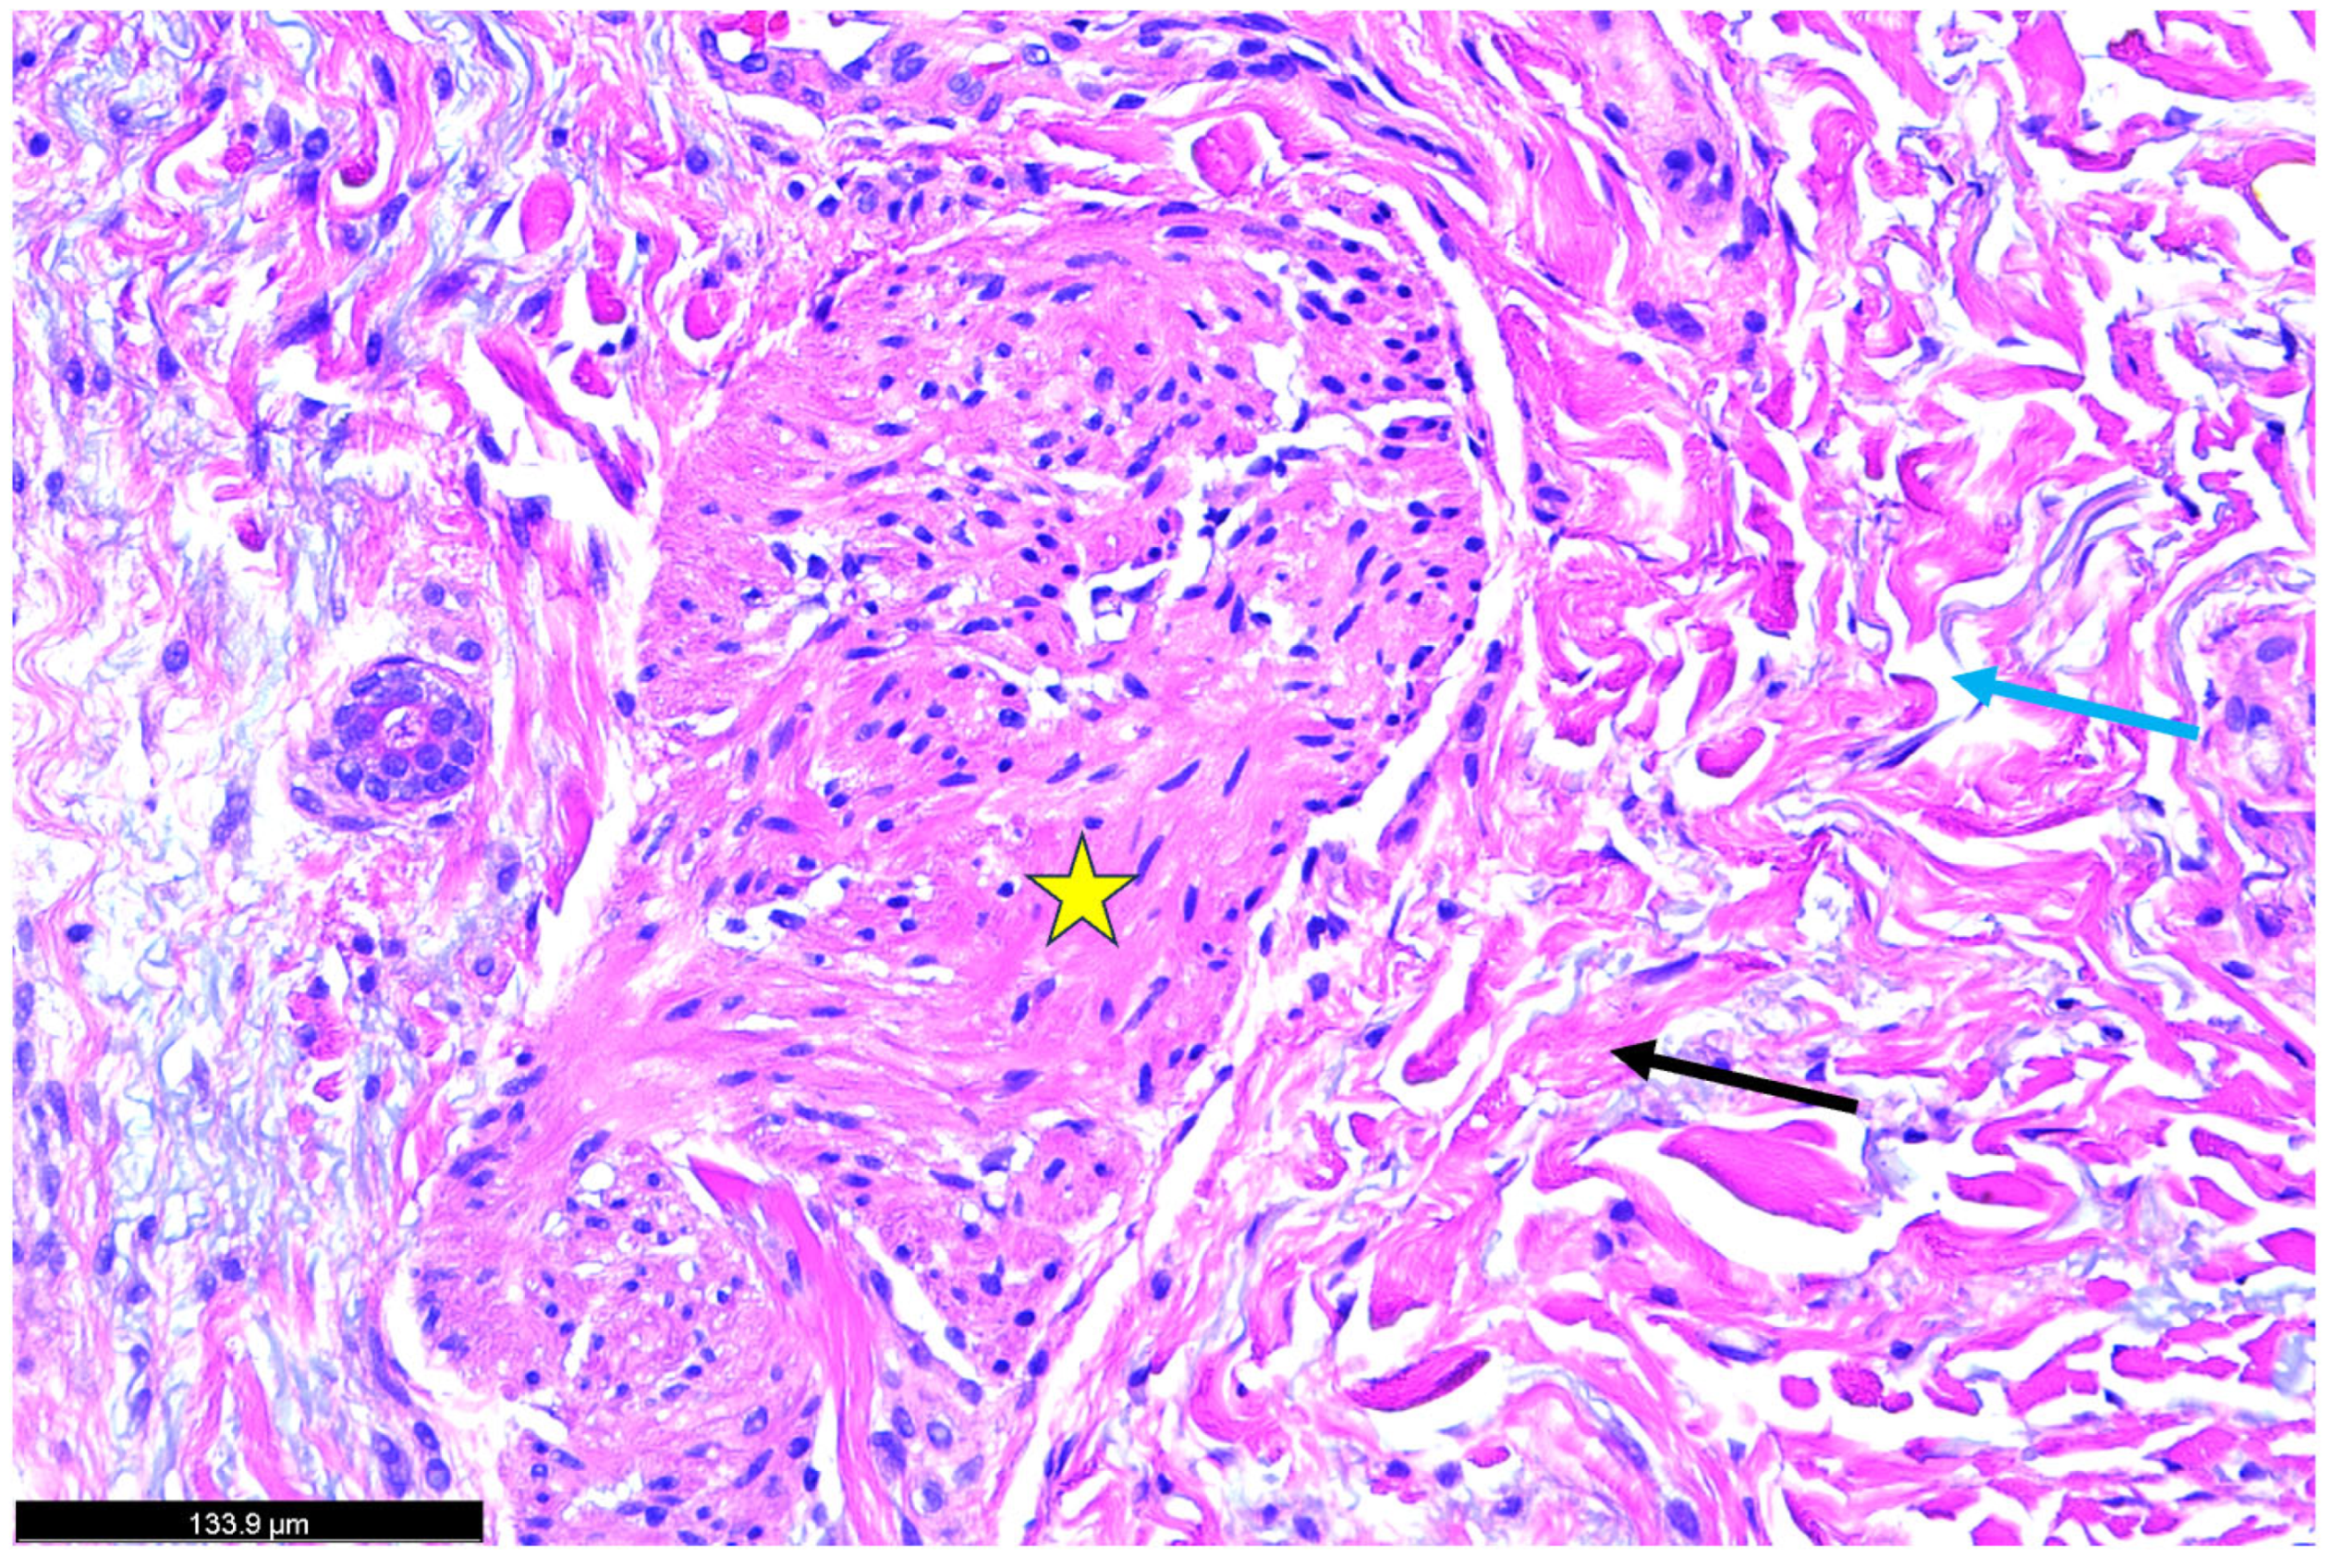

2. Case Study